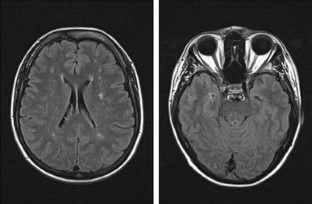

Fig. 2